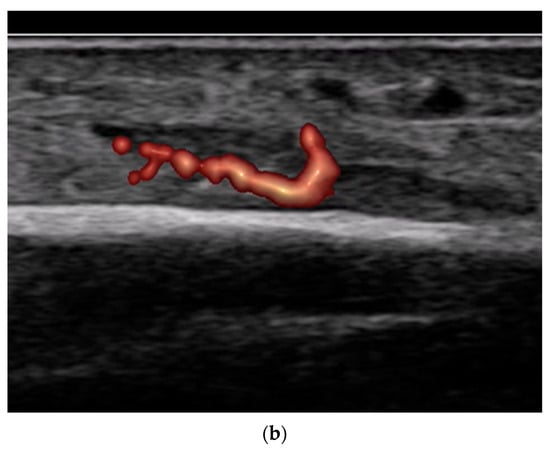

- Use of color and power Doppler: When employing Doppler techniques to assess vascularity related to inflammation or healing, care must be taken to avoid excessive probe pressure. Over compression of the tissue can collapse small vessels, leading to false-negative findings.

- Nerve, fascia and fascial plane blocks

- Recommendation 8: Simple fascia and fascial blocks are highly suited for analgesia in patients with rib and femoral neck fractures. Local anesthesia using nerve blocks and fracture hematoma blocks should be preferred over analog sedation for fracture reduction whenever possible, as they are less risky.

- For simple fascia and fascial blocks, such as rib and femoral neck fractures. Local anesthesia using nerve blocks is preferred to analog sedation for fracture reduction.